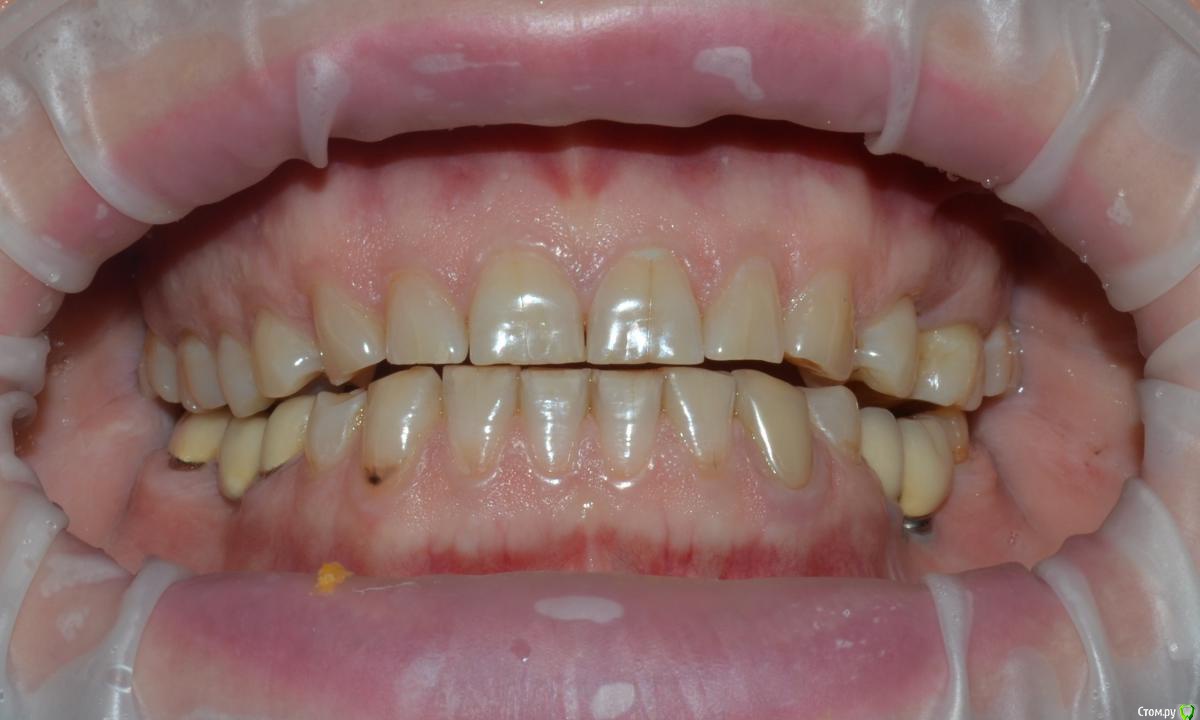

NazranDantist Опубликовано 21 мая, 2015 Поделиться Опубликовано 21 мая, 2015 (изменено) Коллеги поделитесь опытом. Какой план лечения предложить пациентке. Планируется тотальная работа что-нибудь из безметаловой технологии (E-max или претау, еще обдумываем). Вопрос, как выровнять оклюзионную плоскость, нужно ли прибегать к помощи ортодонта? Больше всего интересует первый сегмент, особенно зуб 15, висит слишком сильно. Или все таки стараться выйти из положения керамикой плюс хирургическое удлинение? Изменено 21 мая, 2015 пользователем NazranDantist Ссылка на комментарий

NazranDantist Опубликовано 4 сентября, 2015 Автор Поделиться Опубликовано 4 сентября, 2015 Продолжение кейса. Работа еще не закончена, зуб 25, 35, 36 - аббатменты на подходе, поэтому решили сделать после отпуска пациентки. Фото протокол не соблюдал, курс рубля прыгал, торопился в обменник . Вся работа - имакс на Цереке с редуцированием, фиксация - фронт на чойс, боковые - У-200. Ссылка на комментарий

Freelancer1981 Опубликовано 4 сентября, 2015 Поделиться Опубликовано 4 сентября, 2015 Как цс определяли?Я бы верхние режущий край у верхних зубов(отпрепарированных)загладил,а то разительный контраст с нижними..Фото бы день денька через 3-4.. Ссылка на комментарий

NazranDantist Опубликовано 4 сентября, 2015 Автор Поделиться Опубликовано 4 сентября, 2015 Как цс определяли?Я бы верхние режущий край у верхних зубов(отпрепарированных)загладил,а то разительный контраст с нижними..Фото бы день денька через 3-4..ЦС определял методом джига, высоту "на глаз". Фото сделать нет возможности, пациентка уехала, обещала вернуться Ссылка на комментарий